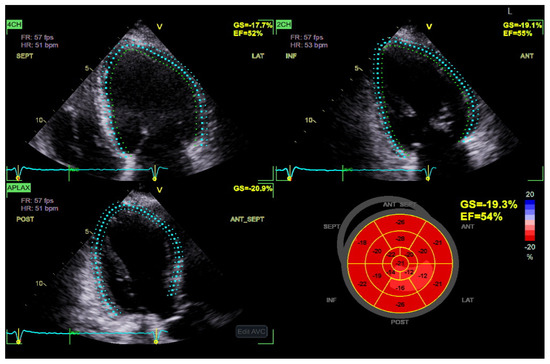

4.1. Speckle Tracking Echocardiography of the LV

STE has emerged as a valuable imaging modality in detecting subclinical myocardial dysfunction in DBCM [68]. Traditional echocardiographic parameters, such as LVEF, often remain within normal limits in the early stages of DBCM, limiting their utility in identifying subtle myocardial abnormalities [69]. In contrast, STE enables the quantification of myocardial deformation by assessing global and segmental strain patterns, thereby offering superior sensitivity in detecting early systolic and diastolic dysfunction [69,70] (Figure 3). Among the various strain parameters, GLS has been extensively validated as a robust marker of myocardial dysfunction. Several studies have demonstrated that diabetic patients exhibit significantly reduced absolute GLS values compared to non-diabetic controls, even when LVEF is preserved [6,71]. A GLS value above −18% is considered indicative of early myocardial impairment, correlating with both metabolic dysregulation and cardiovascular risk [72]. Furthermore, longitudinal strain impairment has been shown to precede changes in circumferential or radial strain, highlighting the vulnerability of longitudinal subendocardial fibers to diabetic metabolic disturbances, fibrosis, and microvascular dysfunction [72,73].

Importantly, GLS also holds significant prognostic value in patients with DBCM. Reduced absolute values of GLS have been independently associated with adverse cardiovascular outcomes, including HF hospitalization, major adverse cardiac events (MACE), and all-cause mortality, even in diabetic individuals with preserved LVEF [74,75]. A longitudinal study by Ersbøll et al. demonstrated that impaired GLS was a stronger predictor of cardiovascular mortality than LVEF in patients with diabetes and established heart disease [76]. Moreover, in asymptomatic individuals with type 2 diabetes mellitus and normal LVEF, subclinical LV dysfunction identified by impaired GLS was shown to be an independent predictor of all-cause mortality and hospitalization over nearly a decade of follow-up [77]. Complementing these findings, reduced absolute GLS has also been linked to myocardial microvascular dysfunction even in the absence of overt fibrosis, suggesting that impaired strain reflects early, preclinical myocardial injury in diabetic populations [78]. The above notions support the incorporation of GLS into routine echocardiographic evaluation for risk stratification in DBCM, facilitating earlier identification of high-risk patients who may benefit from closer surveillance or early therapeutic intervention. As such, GLS offers not only diagnostic but also prognostic utility, reinforcing its central role in the evolving echocardiographic assessment of diabetic myocardial involvement.

Beyond GLS, global circumferential strain (GCS) and global radial strain (GRS) provide complementary insights into myocardial deformation. While GLS typically declines first, GCS and GRS impairments become more evident as the disease progresses [75]. Additionally, segmental strain analysis using STE has revealed that the basal and mid-segments of the left ventricle are more affected in DBCM, which may play a role in diastolic dysfunction and increased myocardial stiffness [79].

Although strain imaging provides greater sensitivity than conventional imaging modalities its accuracy depends on image quality and remains affected by inter-vendor variability. While reference ranges for global longitudinal strain have been proposed, universally accepted cut-off values are still lacking which limits their broad clinical adoption.